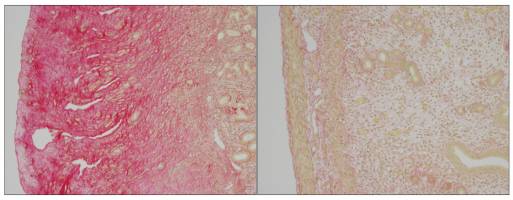

Health - Life Sciences - 12.06.2017

EPFL scientists have identified the biological mechanism behind the painful, potentially lethal, disfiguring Hyaline Fibromatosis Syndrome. Image caption:â?Loss of ANTXR2 leads to the accumulation of extracellular material in mice uterus and sterility (Left). Collagen 6 removal in mice without ANTXR2 restore uterine structure and function (Right).